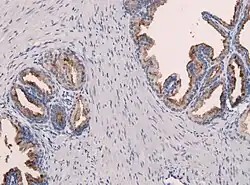

Простатический специфический антиген является полипептидом, состоящим из 237 остатков аминокислот, имеет несколько дисульфидных мостиков. Белок гликозилирован и вырабатывается как нормальными, так и опухолевыми клетками выводных протоков желёз простаты[2][уточнить]. Простатический специфический антиген является протеазой химотрипсинового типа, эта ферментативная функция необходима для разжижения эякулята[14][уточнить][14][уточнить]. В норме небольшое количество простат-специфического антигена поступает в эякулят и секрет простаты и очень незначительное количество попадает в кровь. К экстрапростатическим источникам относят парауретральные железы, молочная железа и амниотическая жидкость[2][уточнить].